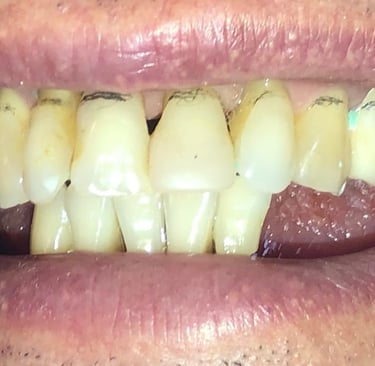

Aspecto Clínico Inicial - Fotografias originais — nenhuma contém retoques

Aspecto Clínico Final - Fotografias originais — nenhuma contém retoques — A cor dos dentes é escolhida de acordo com o gosto e a preferência estética de cada paciente.

Coroas em Dissilicato de Lítio

Todos os caso a seguir estão associadas a clareamento dentário

Depois